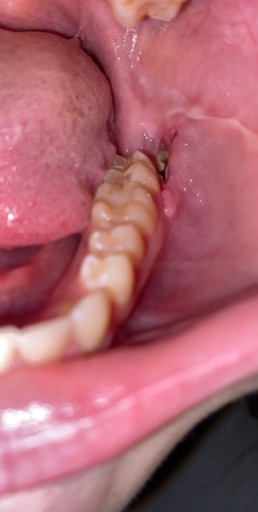

1 week post wisdom teeth removal

Got all 4 wisdom teeth removed exactly a week ago. I thank god didn't really have so much pain, but now I feel like what I think teething may feel like. My head is pounding. I take 3 Advil and 1 extra strength Tylenol before bed and then I usually wake up 3 or 4 in the morning in pain again. Is that normal pain to be feeling? Also the holes where my teeth were have this white stuff no smell is coming from it though. Is that normal? My surgeons office is closed until Monday so any responses would help. Thanks! Report Abuse

It is possible that you have developed a dry socket. This happend when the blot clot is dislodged from the socket exposing bone. It will need to be treated with a medication and packing gauze until it can heal over again. Unfortunately, you need to see your dentist or the oral surgeon to place this medication. It is not available over-the-counter. The white stuff that is covering the sockets is more than likely part of the healing process and you should not be worried. Be sure you are gently rinsing with warm salt water several times a day to keep the area as clean as possible.